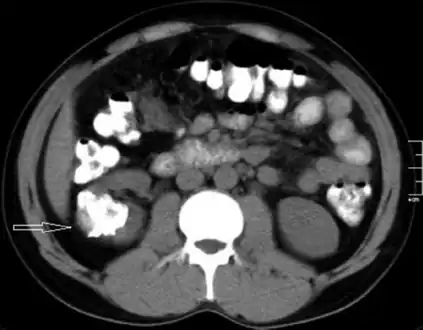

Left flank pain and gross hematuria diagnosed with renal medullary fibroma -